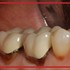

ترمیم و درمان دندان عقل پوسیده

ترمیم و درمان دندان عقل پوسیده، یکی از مسائل مهم و حیاتی در حوزه بهداشت دهان و دندان است که نیازمند شناسایی دقیق و روش‌های مدرن درمانی می‌باشد. ...